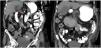

Additional evaluation was carried out by consulting with the internal medicine service. An abdominal computed tomography (CT) scan with oral contrast was ordered that revealed the presence of a hemobezoar in the second and third part of the duodenum, causing acute small bowel obstruction (Fig. 2).

An abdominal CT scan with oral contrast was programmed for one month after her discharge and it showed that the duodenal obstruction had resolved (Fig. 3). The feeding tube was removed, and the patient remained under surveillance.